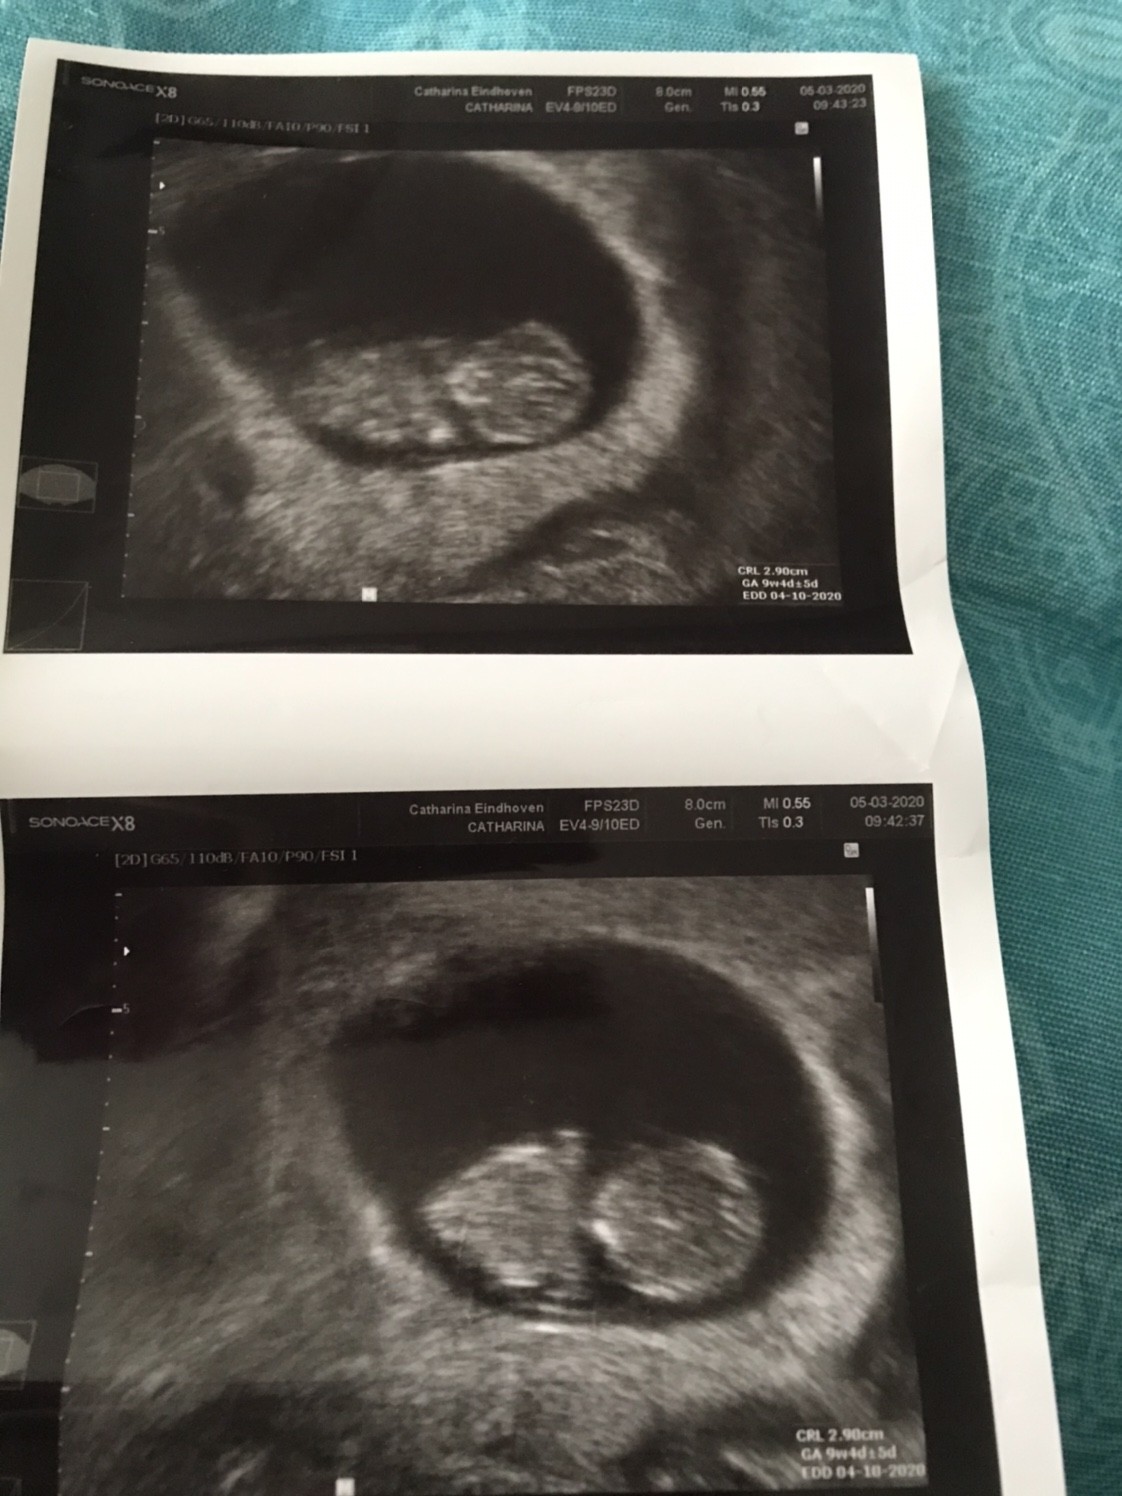

Mamy 2,90cm i jest to 9+4 (wg om 9+5)

Termin porodu wpisany w zaświadczenie o ciąży 4.10.2020

A to nasz model/ka

Zobacz załącznik 1088025

Zobacz załącznik 1088026